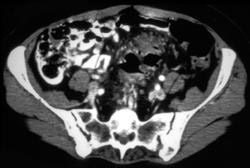

Metastatic Colon Cancer in Gardners Syndrome Patient (subcutaneous Cysts)